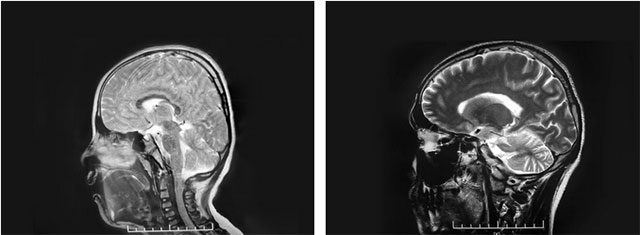

上海藍(lán)十字腦科醫(yī)院神經(jīng)外科6A病區(qū)主任侯增欣主任在詳細(xì)了解文文的病情病史后,對(duì)患兒的頭圍進(jìn)行測(cè)量,結(jié)果為51cm,略小于該年齡段頭圍的參考最低值53cm。頭型從側(cè)面看則呈明顯的“橫窄豎高”,呈“尖頭”形。隨后,通過對(duì)文文顱骨CT的三維重建,可見其冠狀縫、矢狀縫等顱縫已融合,據(jù)此診斷為顱縫早閉。

▲ 患兒頭型(左)與正常頭型(右)對(duì)比